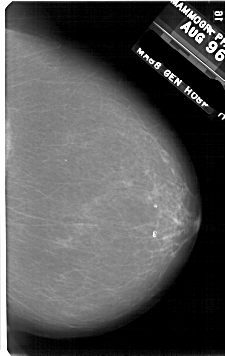

A_1731_1.RIGHT_CC

RIGHT_CC LINES 5326 PIXELS_PER_LINE 3361 BITS_PER_PIXEL 12 RESOLUTION 43.5 NON_OVERLAY